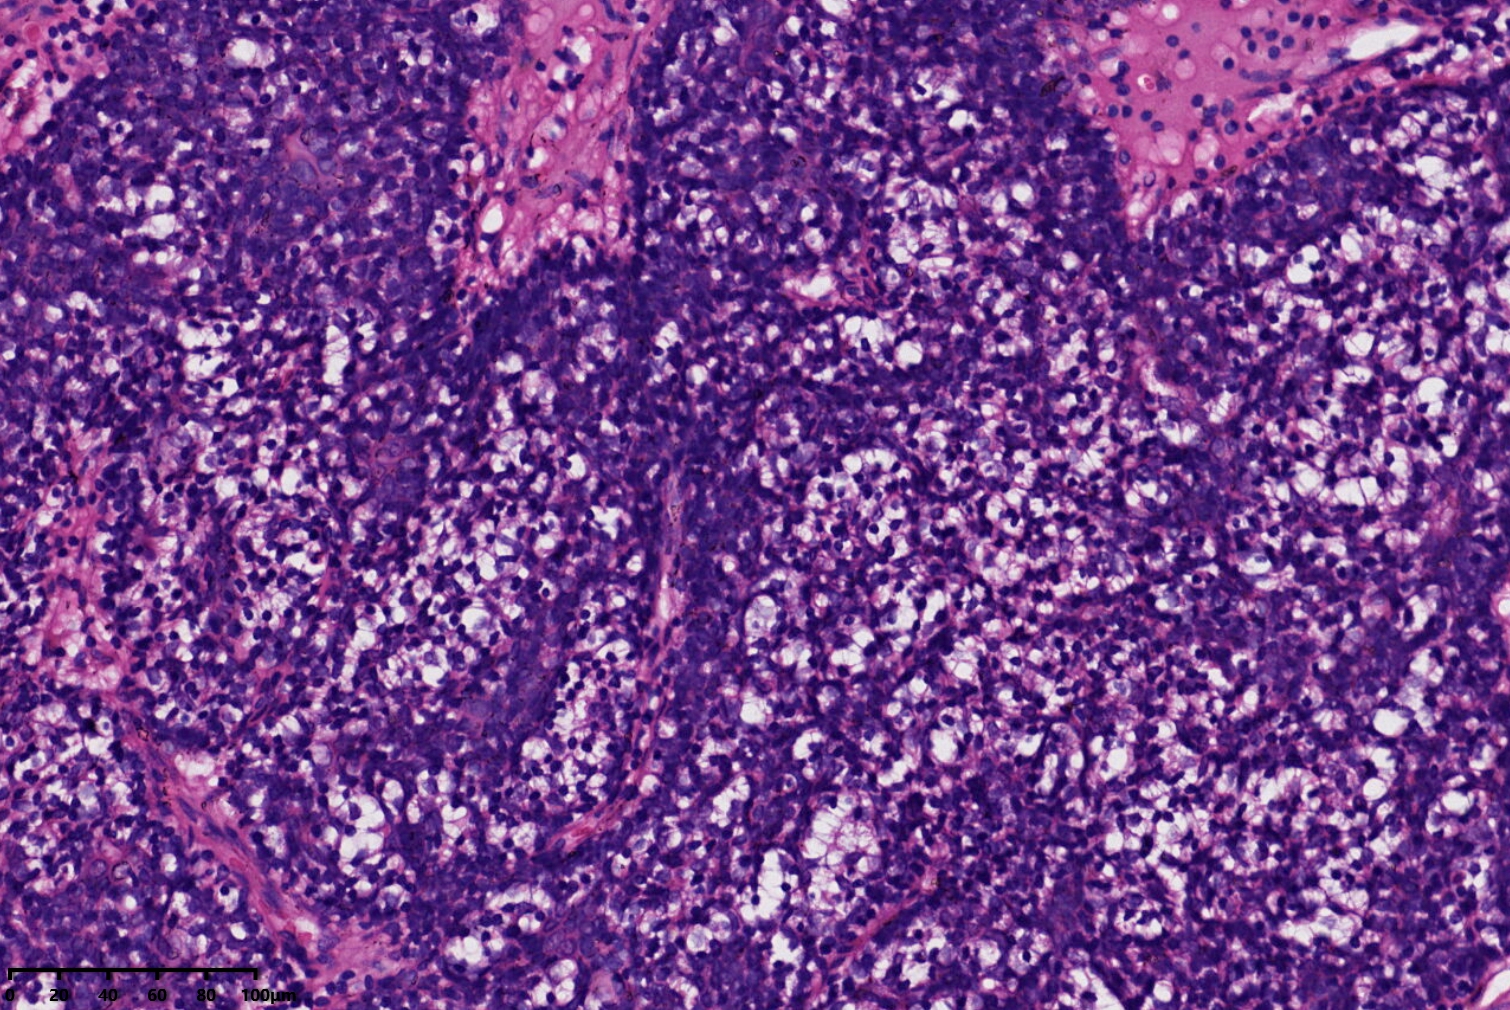

汗腺腺瘤?

背部包块

同意,有的区域像透明细胞汗腺瘤

小汗腺螺旋腺瘤